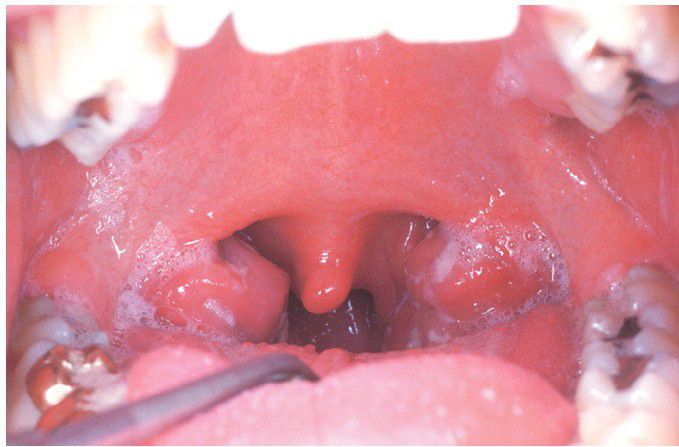

Infectious Mononucleosis

. Hyperplastic pharyngeal tonsils with yellowish crypt exudates.